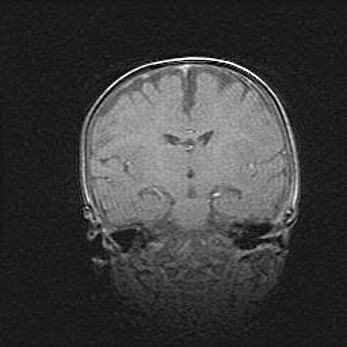

Аномалия Денди-Уокера. Признаки гипоплазии мозолистого тела.

Возраст: 5 месяцев 3 дня

Вес: 5550 г

Пол: мужской

Окружность головы: 39 см

Срок гестации: 40 недель

Аномалия Денди-Уокера – это порок развития головного мозга, для которого характерна триада симптомов: гипотрофия или аплазия червя мозжечка и/или полушарий мозжечка, расширение четвёртого желудочка с формированием ликворной кисты задней черепной ямки, гипертензионная гидроцефалия различной степени.

Гипоплазия мозолистого тела относится к дефектам внутриутробного этапа развития мозговой ткани, возникающим в процессе закладки структур головного мозга, что происходит на начальных этапах развития эмбриона.